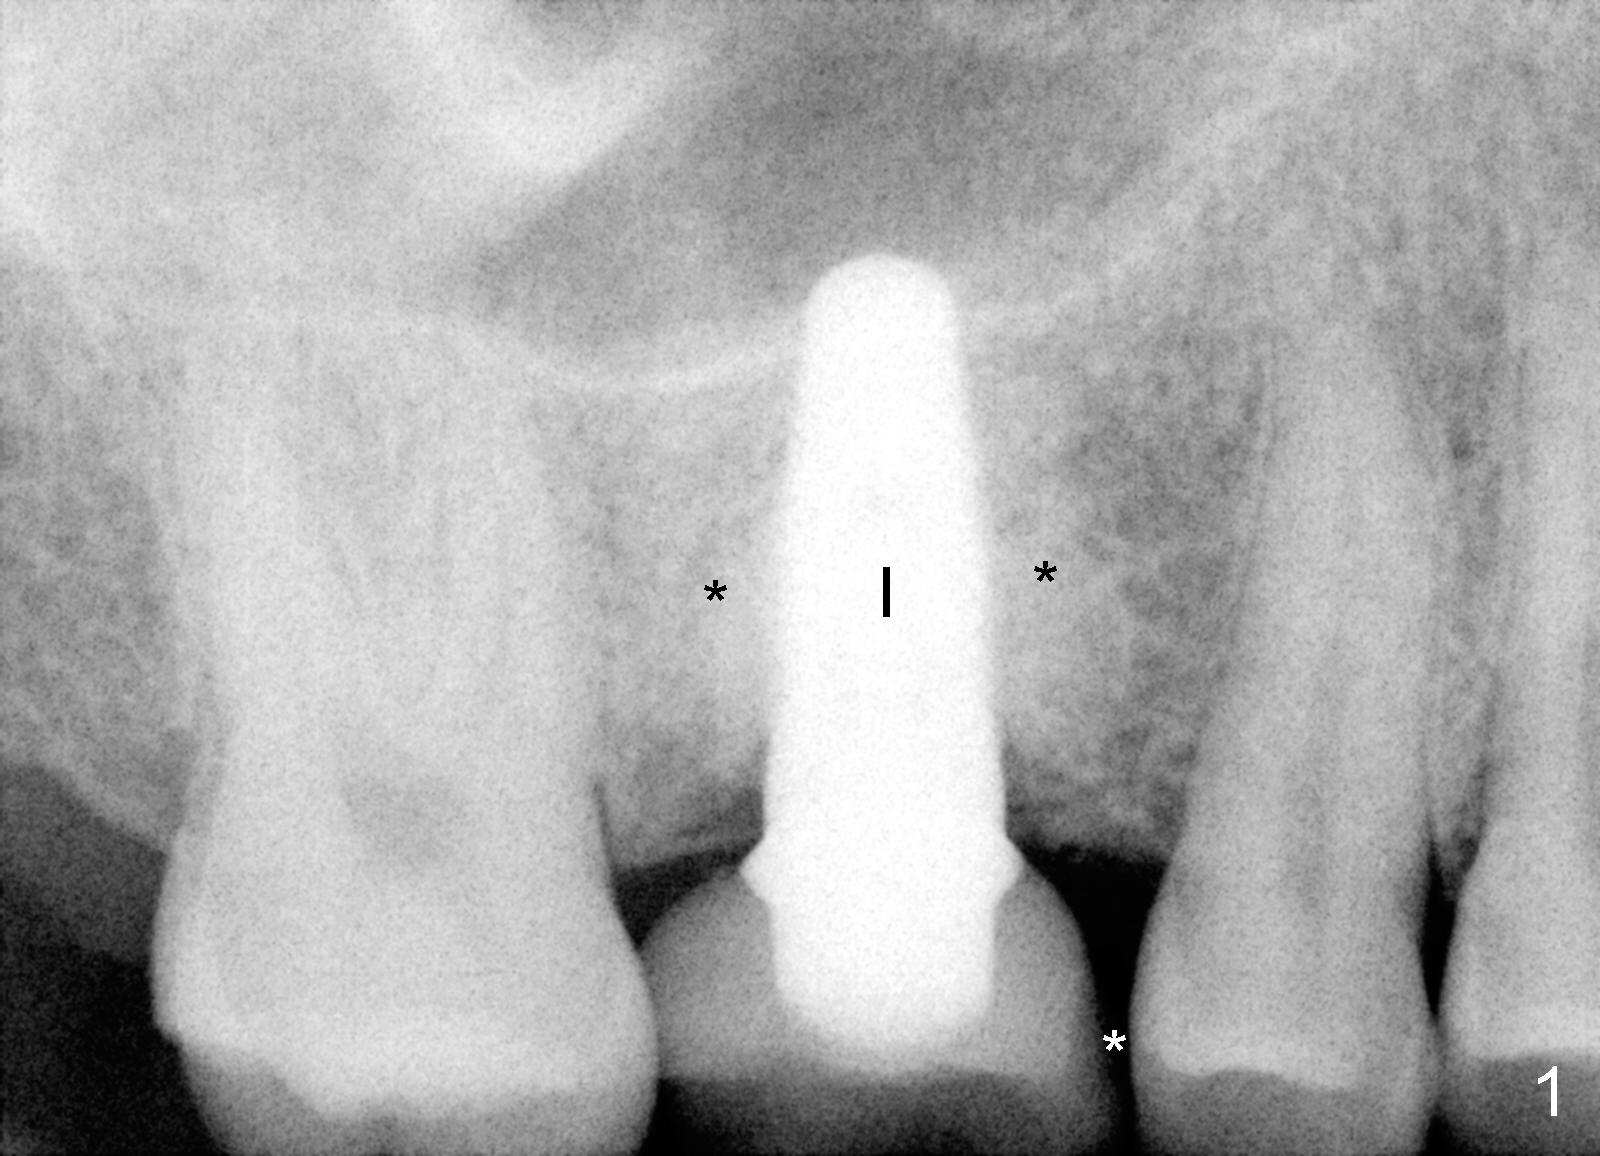

Three years after new crown fabrication, the mesiolingual cusp of the PFM fractures (Fig.3 blue outline). This time, the patient has no problem eating, since the contact is not lost. X-ray shows that the mesial portion of the porcelain is not supported by metal framework (Fig.4 ^). Our treatment plan is first to restore the missing tooth #18.